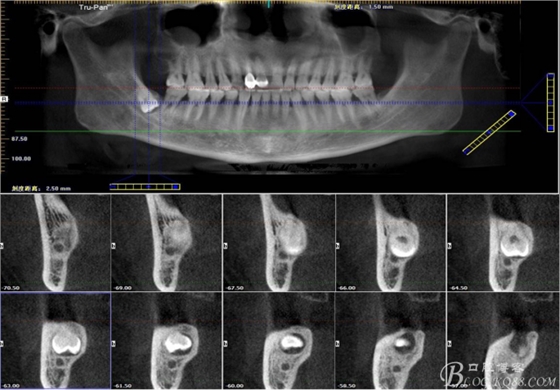

二、術(shù)前CBCT影像:

圖1.47牙冠的近中面緊鄰下頜神經(jīng)管

圖2.判斷47牙根是否吸收

圖3.通過矢狀面和冠狀面來判斷48與下頜管及47的關(guān)系

圖4.水平方向48與47之間的關(guān)系

圖5. 48的三維視圖

圖6.測量48頰、舌側(cè)骨板厚度。

圖7.測量牙冠近遠(yuǎn)中徑的大小及遠(yuǎn)中骨板的厚度